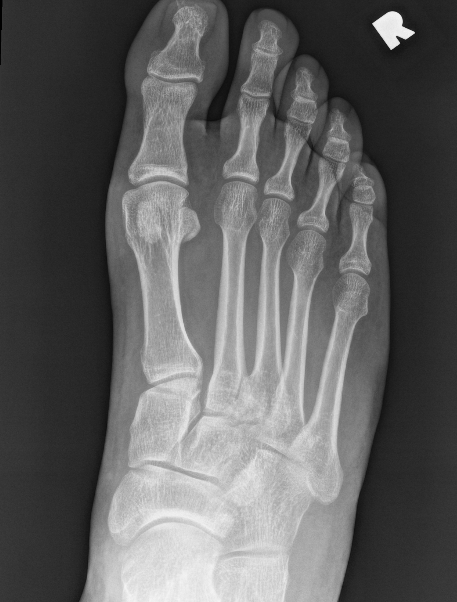

Widening of the medial cuneiform - 2nd metatarsal distance, inter-metatarsal diastasis, fleck sign, possibly increased inter-cuneiform distance

Widening of the medial cuneiform - 2nd metatarsal distance, inter-metatarsal diastasis, fleck sign, increased inter-cuneiform distance